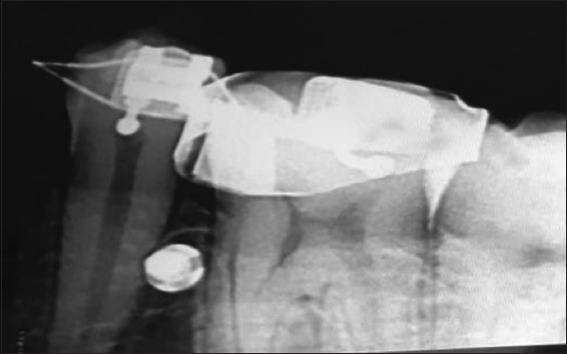

An institutional ethics committee approved this prospective two-group experimental study. Split mouth treatment was performed on 16 patients; 18–22 years old with healthy periodontium, good oral hygiene, and whose treatment plan included implant placement between mandibular 1st molar and 2nd premolar was chosen for this study from the department with patients’ informed consent. To eliminate the errors that could compromise the success of implant placement and the quality of the implant stability quotient (ISQ) reading and a stent was made out of 0.019 × 0.025” stainless steel for implant implantation. The stent’s entire length (from the bracket location) was limited to 9 mm, and its loop was 4 mm in diameter. The micro-implant was positioned 7 mm above the alveolar crest. The mesial and distal horizontal legs were ligated to the premolar bracket and molar tube respectively [Figure 1] after stent engagement, the area of the micro implant insertion was cleaned with povidone-iodine. A topical anesthetic was applied. With full retraction of the soft tissue, 0.5 ml of anesthetic solution (Lignocaine with adrenaline) was infiltrated in the mucosa. The insertion site was then evaluated with a probe to check if the area was anesthetized. This also serves as a visual marker for inserting the micro implant.

thumb

Figure 1: Stent engaged into premolar bracket and molar tube